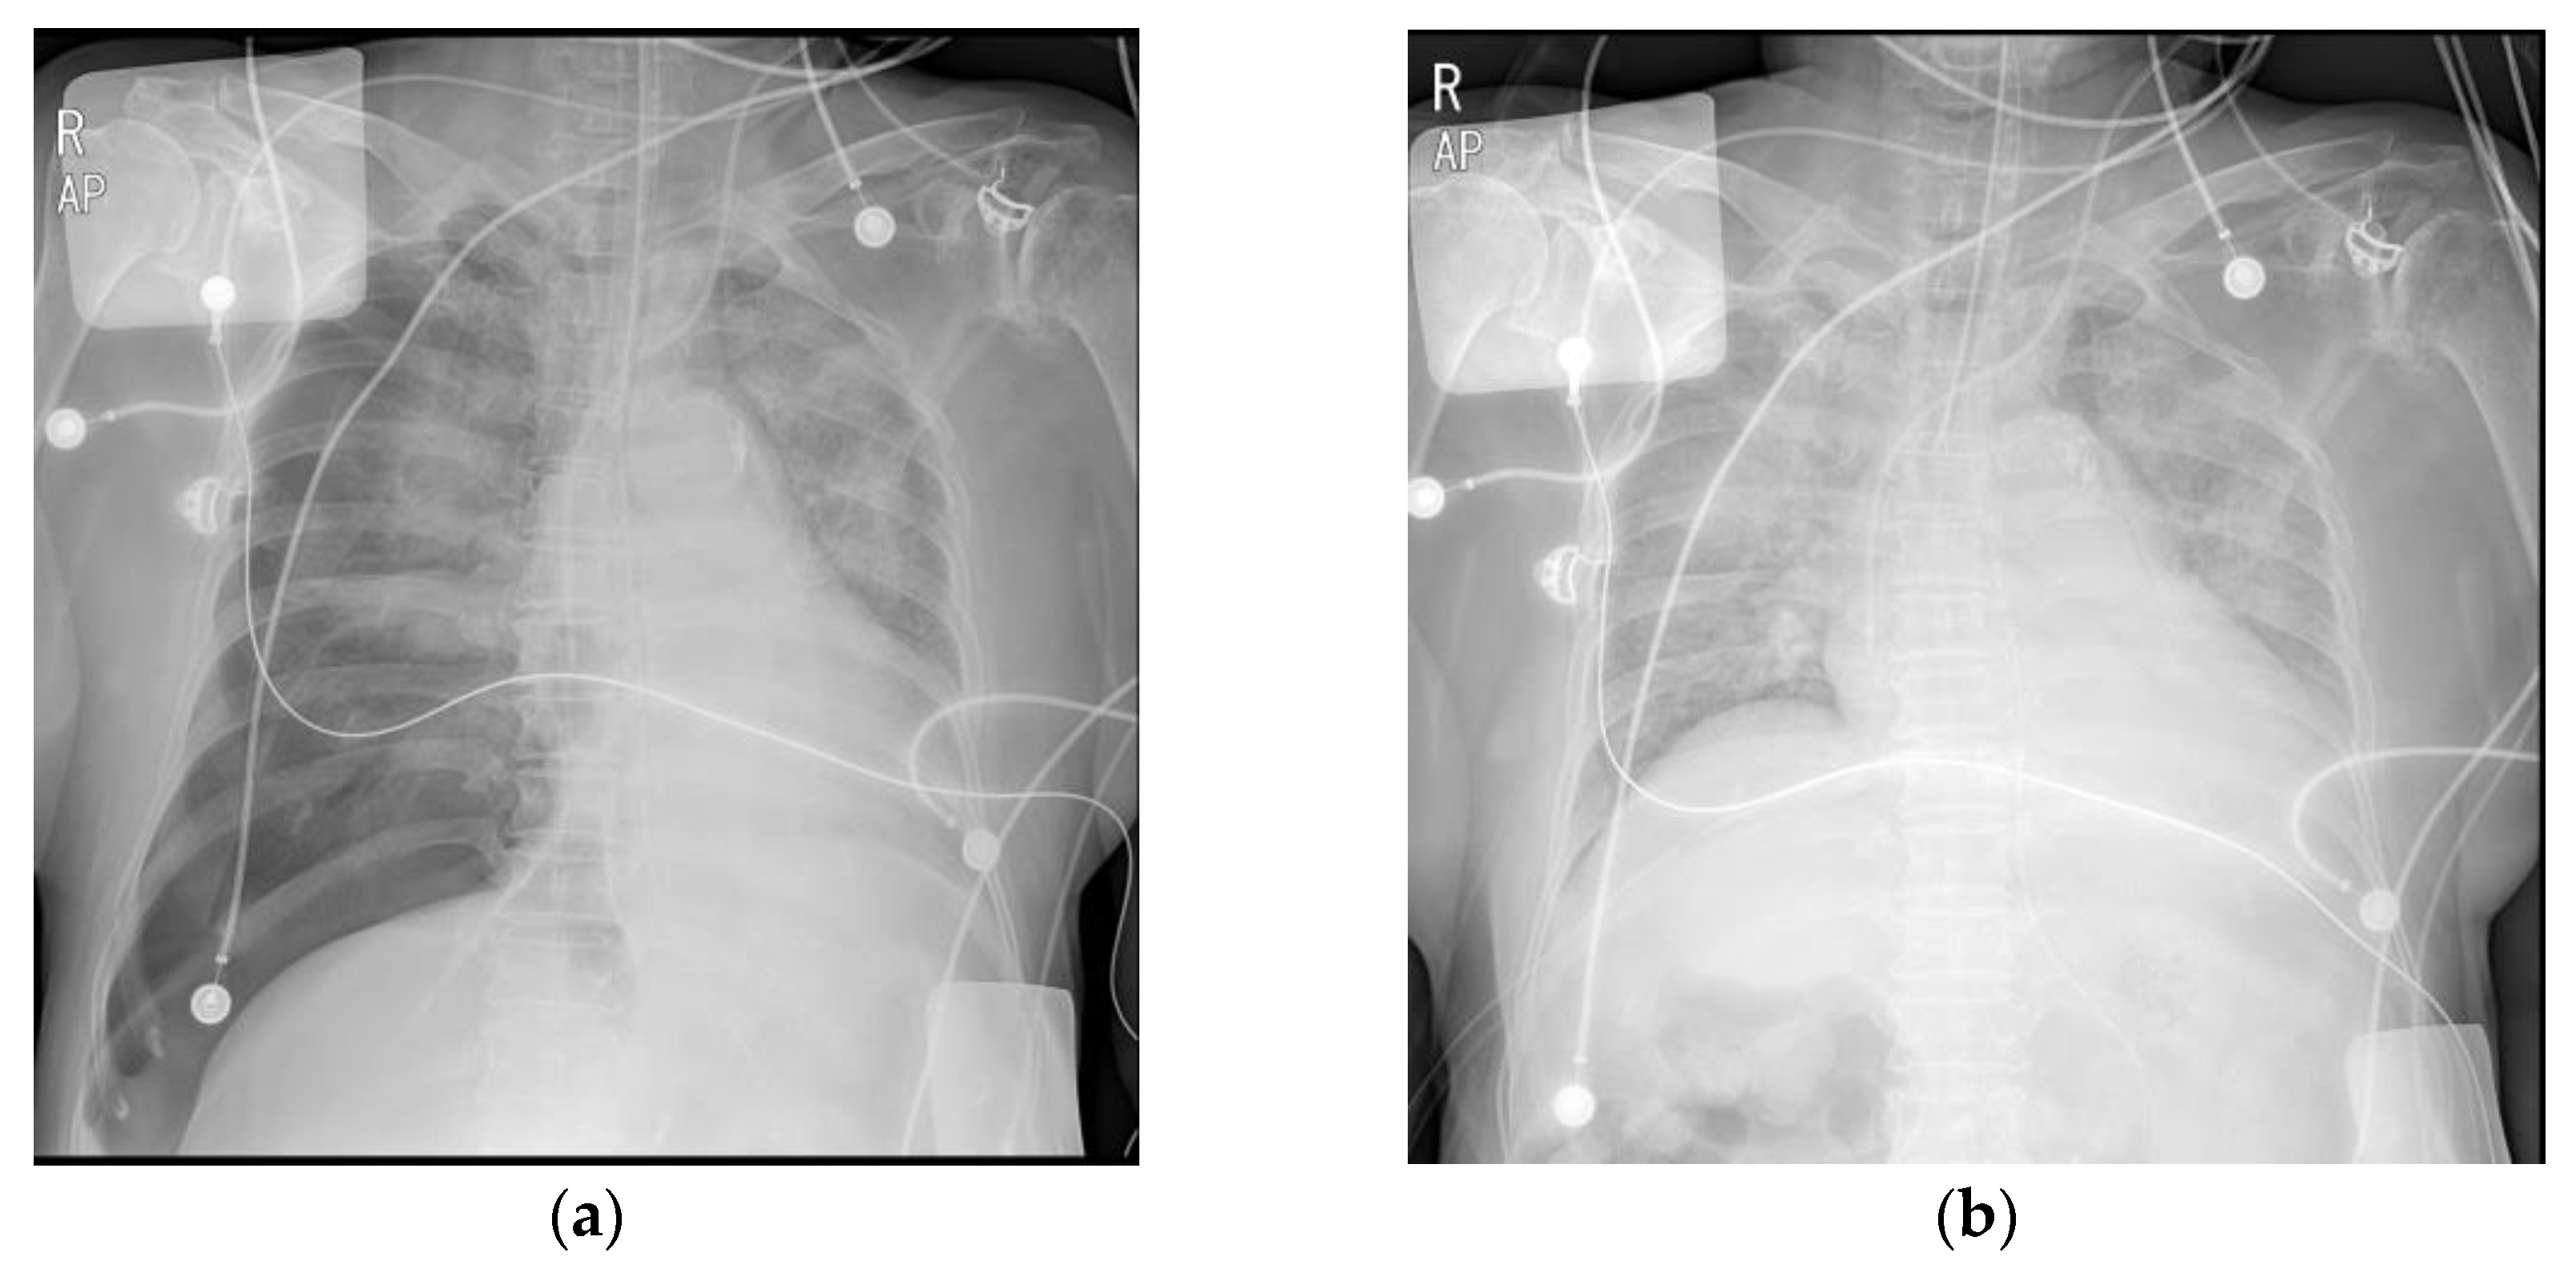

Selective right lung intubationventilation strategy in persistent left Intubation And Pneumothorax the duration of chest intubation among those with pneumothorax varied between 2 and 15 days (median 7). historically, a small pneumothorax has been shown to be successfully treated without chest tube. pneumothorax is especially likely if there is right main bronchus intubation. pneumothorax is a potentially lethal complication associated with. Intubation And Pneumothorax.